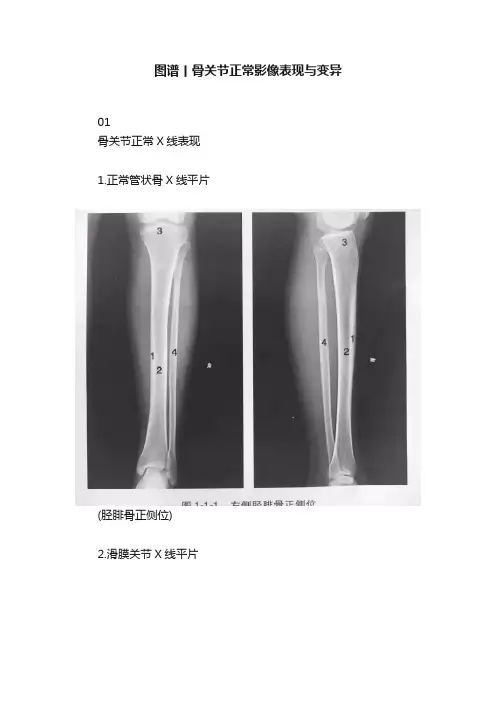

1.正常管状骨X线平片

(胫腓骨正侧位)